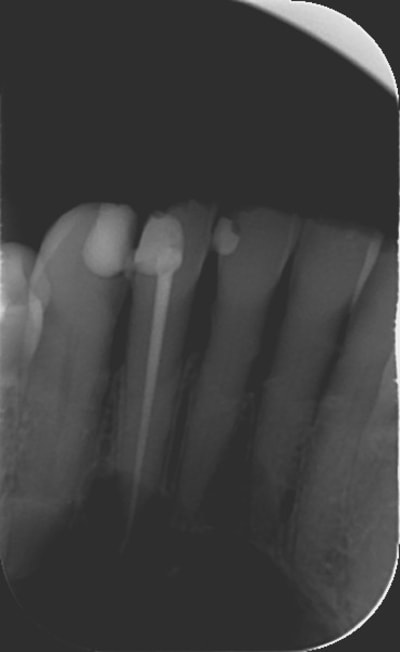

ps : désolé pour la qualité des radios / j'ai pas réussi à faire de belles radio sur cette patiente, qui est vraisemblablement réfractaire au contraste (en plus d'avoir bougée lors de la pano faite avec les boucles d'oreilles)

joli kyste....mais là maintenant tu as un risque de fracture mandibulaire+++

Elle a été envoyé, par son dentiste, à l’hôpital pour un scanner, et l'interne qui l'a vue, lui a dit qu'elle n'avait rien, et qu'il fallait juste que son dentiste refasse éventuellement le traitement canalaire de sa 42.

l'image de la première radio de la deuxième serie.... bizarre...

Pas besoin d'un chir maxillo pour çà, la pano déforme énormément. Le risque de fracture est assez peu important car l'os basal n'est pas atteint. Un chir oral ou un MBD s'en sortira sans pb, "suffit" d'ouvrir par 2 incisions de décharge en avant des trous mentonniers et décollement du lambeau, on tombe sur la bête directement, en général çà n'est retenu que par l'apex en cause que l'on sectionne et hop anapath de principe et on referme. Le plus long c'est de suturer correctement. LBFA030, 73,21€, mdr...